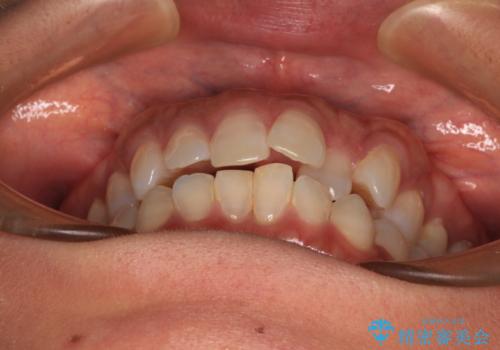

クロスバイトを治したい インビザラインによる矯正治療

- 前歯のクロスバイトを気にして来院された患者様です。

上下ともに、前歯部を中心にやや叢生が認められる程度であったため、ワイヤーでもインビザラインでも、どちらでも対応可能な状態でした。